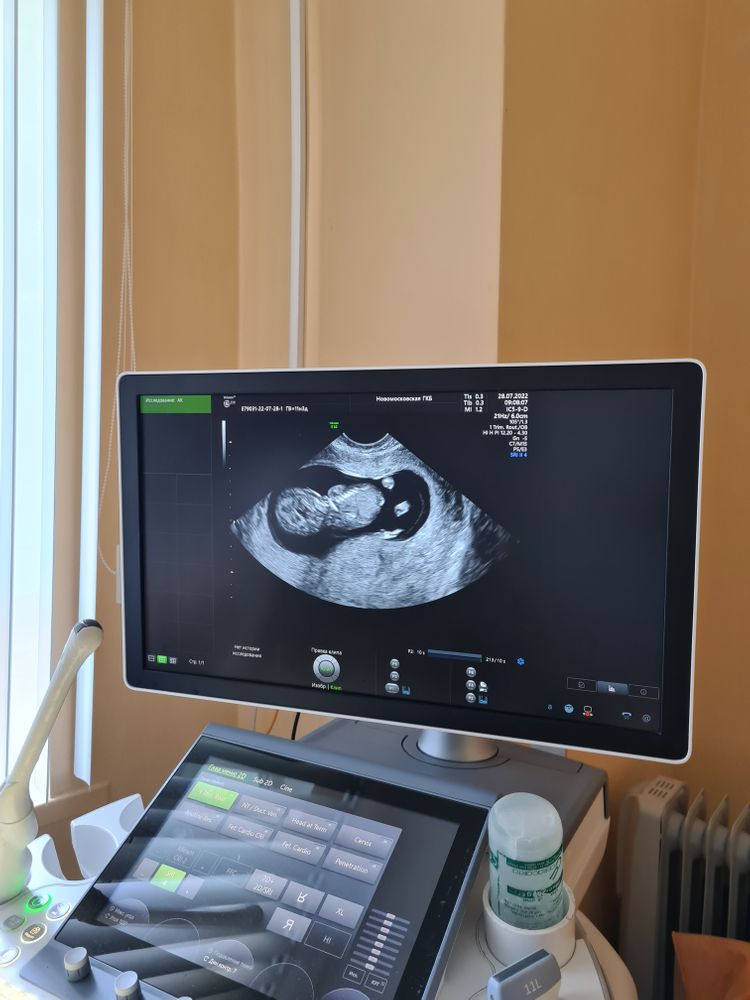

Может кто понимает, мальчик или девочка?) На кого похоже ?

Плод лежит спинкой. С такого ракурса, конечно, не видно.

Я тоже не понимаю обычно что и где))) Это первый скрининг?🥰

Женевьева, да) Тоже вообще ноль в этом)

Anna , Ну дальше будет попонятнее) Вам не предположили даже кто?)

Женевьева, я спросила, узист сказала на втором узи узнаешь. Бесплатная поликлиника 😄

Так малыш спиной на фото) Ничего не видно)